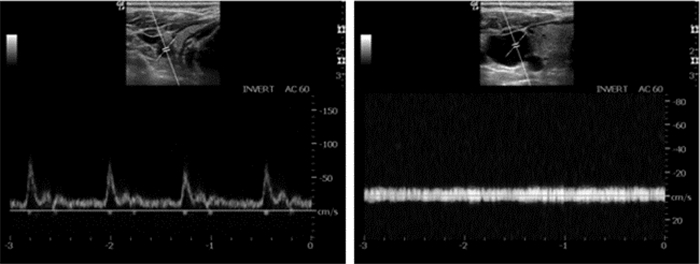

无论是动脉还是静脉在超声下都显示为圆形或椭圆形液性暗区,由于静脉血管缺乏富含弹性纤维的中膜,管壁较薄,相对于伴行的动脉更容易被压瘪,因此可以通过探头加压的方式来观察,首先被压瘪的是静脉(图 16)。打开超声的脉冲多普勒血流显像,可见动脉血流呈搏动样高频信号,而静脉血流呈连续性低频信号(如图 17)。

| 图 16 加压法辨别动静脉(左图为加压前;右图为加压后静脉压瘪) |

| 图 17 脉冲多普勒超声辨别动静脉(左图为颈动脉血流图;右图为颈静脉血流图) |